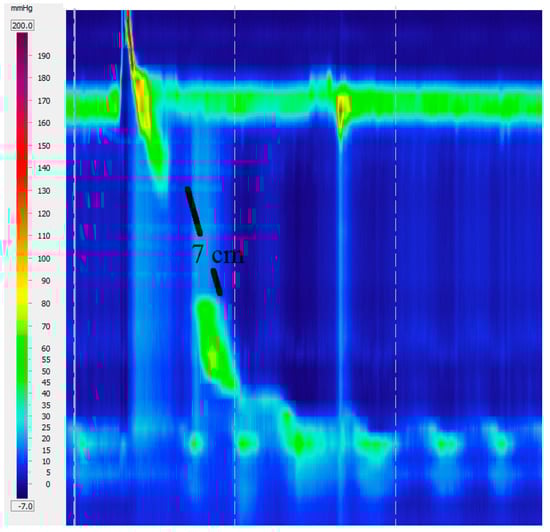

4.2. Hypercontractile Esophagus